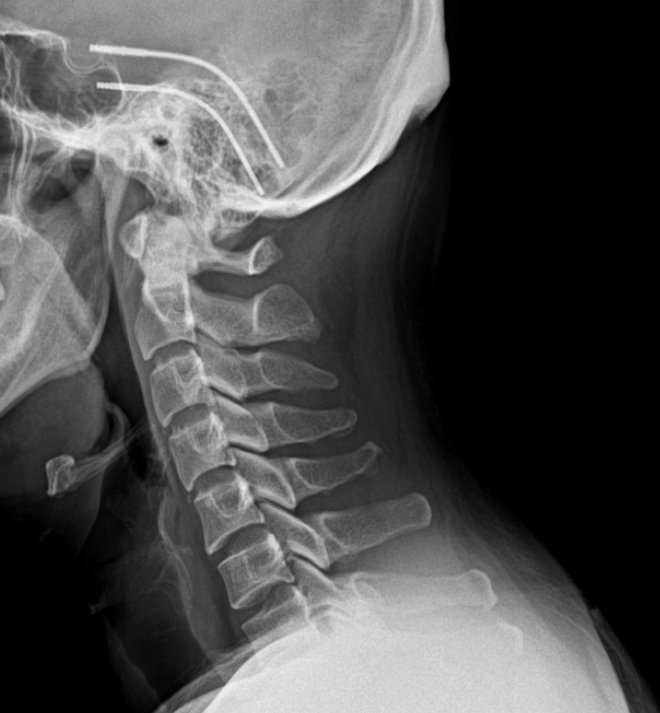

거북목교정기 지긋지긋한 만성 통증 벗어난 후기

거북목교정기를 애타게 찾아 사용하게 된 계기가 있었어요. 벌써 3년 째 이 지긋지긋한 통증으로 고생을 하...

거북목 자세교정기 얼라인비 사용후기

거북목교정기, 자세교정기 얼라인비 사용후기 출산 후 허리가 자주 아프다보니 저도 모르게 자꾸만 구부정...

거북목 교정기 효과 보기 위해서 꼭 봐야하는 이유

평소 핸드폰을 오래 하고 일할 때도 바르지 못한 자세로 컴퓨터를 사용하다 보니 거북목이 점점 심해져서 ...

거북목 교정기 통증 완화에 알맞게 사용한 후기

컴퓨터 개발자로 일하고 있는 저는 취업 이후에 끊임없는 프로젝트와 야근으로 인해서 나날이 거북목 증상...

거북목 교정기 사용의 모든것, 목 뻐근함 탈출!

평소에 앉아서 컴퓨터 작업을 많이 하다 보니 어느새 거북목이 생겨나기 시작했습니다. 처음에는 별 문제가...

거북목 교정기 운동 효과 상승시키는 3가지 구매기준 필독

거북목 교정 운동보다 효과 좋은 거북목 교정기 추천 현대인이라면 거북목 없는 사람이 없다지만 나는 유독...

거북목 교정기 이건 알고가야 제대로된 효과를 볼 수 있어요

공장에서 물건을 분류하는 업무를 보고 있다 보니 정확하게 하기 위해서 자세히 들여다보려고 하면 자연스...

거북목 교정기 커브가 살아나는 효과를 보고싶다면

매일 앉은 자리에서 화장실 갈 때를 제외하고는 키보드를 두드리고 있는 생활을 하다 보니까 업무에 집중하...

거북목 교정기 확실한 효과를 위해 필수적인 것은?

매일 같이 컴퓨터 앞에 앉아서 자판만 치니까 집중하다 보면 저도 모르게 목이 앞으로 나와 있어서 변형이 ...